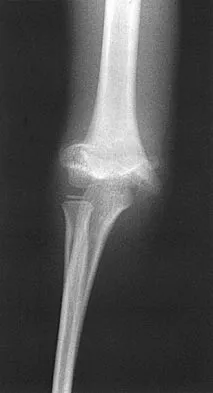

Figure 27 shows the radiograph of a 26-year-old man who sustained a closed head injury and a closed elbow dislocation 6 weeks ago. Examination reveals 65 degrees to 115 degrees of flexion, and intensive physical therapy has resulted in no improvement. A decision regarding the timing of surgical correction of the contracture should be based on

Explanation

The patient has heterotopic ossification, a more common finding in patients who have sustained head injuries. Treatment will require removal of the heterotopic bone and anterior and posterior capsulectomies. The main concern about timing is the possible recurrence of heterotopic bone. While an extended wait was once thought necessary, this is no longer true. The timing is based on the time since injury and evidence of bone maturation on plain radiographs. A sharp marginal demarcation of the new bone and a trabecular pattern within it are usually present 3 to 6 months after onset, indicating that it is safe to proceed with surgical excision. It is not necessary to wait more than 6 months. Bone scan results are not good indicators because they may remain "hot" for long periods of time. The levels of alkaline phosphatase and serum calcium-phosphorus product do not need to be measured.